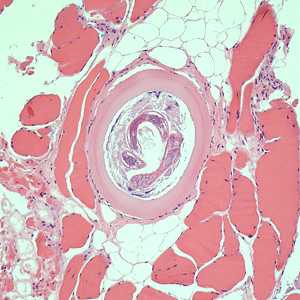

A hunter prepared dried jerky from fresh bear meat and provided some to a group of friends. Most developed moderate to severe abdominal pain, nausea, and fatigue within 48 hours. Some of the bear meat was submitted for laboratory testing. Images of stained histological sections of bear meat were sent to the DPDx Team for confirmation of parasites. Figures A and C were taken at 200x magnification; Figures B, D, and E were taken at 400x magnification. What is your diagnosis? Based on what criteria?

The objects observed in the meat were larvae of Trichinella sp. Diagnostic features included;

- the presence of encapsulated, coiled nematode larvae within the meat (encapsulation is consistent with some Trichinella spp.)

- the presence of nucleated stichocytes (Figure E; arrow).